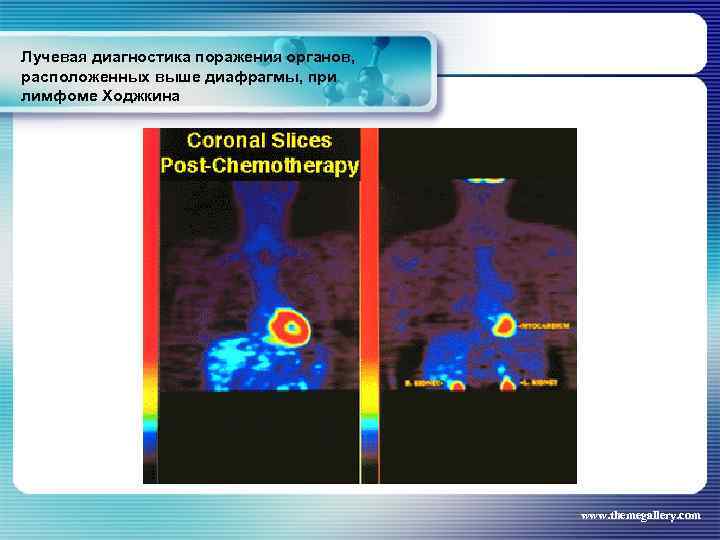

Лучевая диагностика поражения органов, расположенных выше диафрагмы, при лимфоме Ходжкина Частота поражения органов грудной полости при лимфоме Ходжкина: поражение средостения легких плевры грудной стенки - 66, 7 % 33, 75% 5, 3% 1, 8% www. themegallery. com

Лучевая диагностика поражения органов, расположенных выше диафрагмы, при лимфоме Ходжкина Частота поражения органов грудной полости при лимфоме Ходжкина: поражение средостения легких плевры грудной стенки - 66, 7 % 33, 75% 5, 3% 1, 8% www. themegallery. com